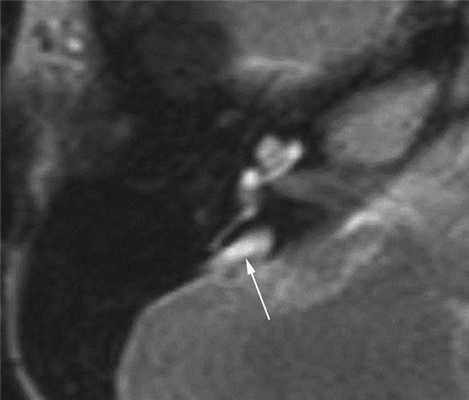

При наличии сенсоневральных нарушений слуха неясной этиологии показано выполнение МРТ головного мозга и пирамид височных костей. Т2-взвешенные изображения позволяют отчетливо выявить расширенный водопровод преддверия (рис. 3).

Рис. 3. Широкий водопровод преддверия (стрелка). Магнитно-резонансная томограмма правой височной кости в аксиальной проекции. Пациент А., 14 лет.

1. Пациент А., 14 лет (аудиограмма, рис. 4), наблюдается в отделении нефрологии Научного центра здоровья детей с диагнозом: нефротический синдром, дистальный почечный тубулярный ацидоз. Снижение слуха возникло внезапно, без видимых причин, в возрасте 13 лет 6 мес. На компьютерной томограмме височных костей — двустороннее расширение водопровода преддверия (см. рис. 2). Высокоразрешающая МРТ пирамид височной кости также выявила широкий водопровод преддверия (см. рис. 3). Рекомендовано использование системы BICROS.